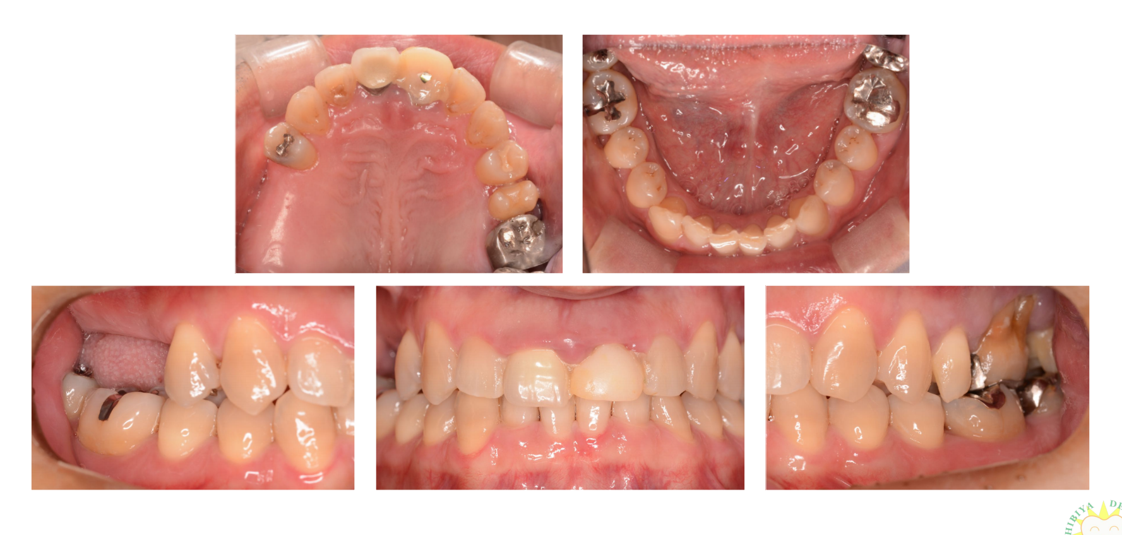

インプラント治療の症例2

(右下奥歯がない)

治療前

治療後

| 診断名・主訴 | ①右下に歯を入れたい |

| 年齢 | 41歳 |

| 治療期間 | 5ヶ月 |

| 治療内容 | インプラント治療 |

| 治療に用いた主な材料、設備機器 | 京セラFINESIAインプラント 上部構造:ジルコニアセラミック |

| 抜歯部位 | なし |

| 治療費 | 約80万 |

| リスク・副作用 | 術後出血や腫れ |

インプラント治療の症例3

(右上奥歯がない)

| 診断名・主訴 | ①右上インプラント希望 |

| 年齢 | 71歳 |

| 治療期間 | 7ヶ月 |

| 治療費 | 約100万 |